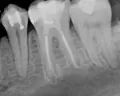

Стал беспокоить зуб под пломбой, на пломбе была трещина. Пошла к стоматологу, оказалось глубокий кариес под пломбой, поставила новую пломбу. После этого зуб стал болеть, больно при надкусывании. Пришла опять к стоматологу, сказала, давайте опять пломбу поменяем. Оказалось, что она в прошлый раз не до конца дочистила, там был еще кариес. Поставила пломбу, надкусывать не больно стало, но зуб побаливать. Пришла опять, сказала депульпировать надо. Почистила каналы, поставила временную пломбу. Вот вчера запломбировала каналы. Сделала снимок. Стоматолог сказала, что каналы запломбированы хорошо. Но мне кажется, что как будто не до конца они запломбированы, по снимку.

Хорошо ли запломбированы каналы?

Действительно возможно, что канал не до конца запломбирован.